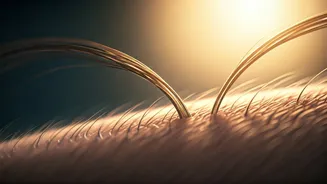

However, not everyone facing thinning hair is an ideal candidate for this surgical procedure. The success of a transplant hinges critically on the availability and health of the 'donor area,' typically located at the back of the scalp. This region must possess dense, robust hair follicles that are genetically resistant to balding. Women experiencing severe, widespread thinning across the entire scalp (diffuse thinning) or those with an active, inflamed scalp condition may not benefit from a transplant, as the donor hair might not be robust enough to survive the process. Conversely, women with localized thinning, a receding hairline, or hair loss due to traction alopecia (from tight hairstyles) are often excellent candidates. Additionally, women with stable Female Pattern Hair Loss (Androgenetic Alopecia) who maintain a strong donor area can expect remarkable, life-enhancing results. Careful assessment by a qualified surgeon is paramount to determine individual suitability.

Beyond the short-term, manageable side effects, it's important to be aware of rarer but potentially more serious complications associated with hair transplantation. Infections can occur if the healing sites become contaminated by bacteria. Folliculitis, characterized by inflamed, pimple-like bumps, or even cysts from ingrown hairs, can arise as new hair follicles begin to emerge through the skin. Scarring is an inevitable outcome of any hair transplant. The FUT (Follicular Unit Transplantation) method, which involves removing a strip of scalp, results in a linear scar at the back of the head. The FUE (Follicular Unit Extraction) technique, where individual follicles are harvested, leaves very small, dot-like scars. The visibility of these scars depends on individual healing patterns. An unnatural appearance is also a risk if the surgeon lacks experience; transplanted hairs might not align with the natural growth direction, or density might be inconsistently matched, leading to a patchy look. The most severe, though exceedingly rare, complication is scalp necrosis, a condition where a section of skin dies due to inadequate blood supply, often linked to heavy smoking or pre-existing vascular issues.